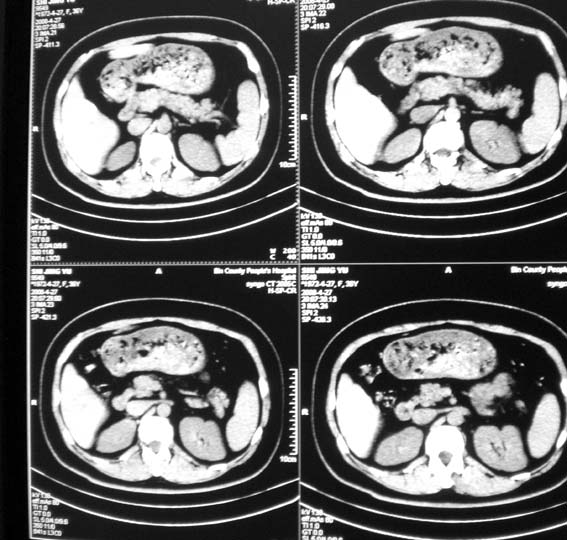

标题: CT13126:腰痛,肾区痛。

女,36岁,腰痛,肾区痛曾有肾囊肿史。

中上腹部ct平扫未见明显异常。

可行强化帮助检查